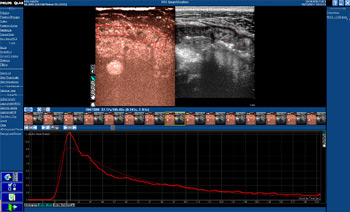

Ультразвуковое исследование тонкой кишки с внутривенным контрастным усилением при болезни Крона.

|